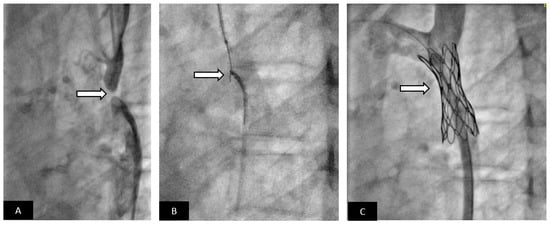

- Valverde, I.; Gomez, G.; Coserria, J.F.; Suarez-Mejias, C.; Uribe, S.; Sotelo, J.; Velasco, M.N.; Santos De Soto, J.; Hosseinpour, A.R.; Gomez-Cia, T. 3D printed models for planning endovascular stenting in transverse aortic arch hypoplasia. Catheter. Cardiovasc. Interv. 2015, 85, 1006–1012. [Google Scholar] [CrossRef] [PubMed]